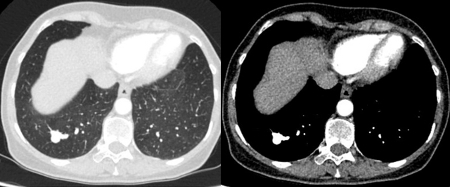

Computed tomography (CT) sections from two cases with benign perifissural nodules. Note the smooth margins and the normal undisturbed adjacent fissure

From the collection of Dr George Tsaknis, MD, PhD, FRCP(London), MRQA, MAcadMEd, PGCert; used with permission